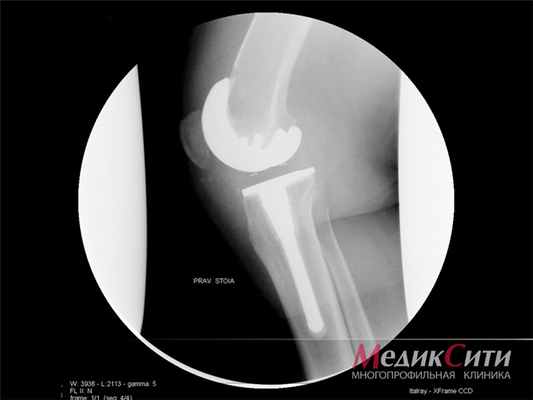

(Слева) Рентгенография в ПЗ проекции: выраженная остеопения и умеренное сужение медиального отдела сустава у пациента с РА и впервые возникшей болью. Также обратите внимание на две склеротичные линии в структуре медиального мыщелка большеберцовой кости. Они являются диагностическими признаками патологического перелома.

(Справа) Рентгенография в ПЗ проекции является классическим методом исследования при РА. Визуализируются общее сужение суставного пространства и выраженная остеопения. Кроме того, имеется слабость связок, что определяется по медиальному смещению большеберцовой кости относительно бедренной кости. Также обратите внимание на характерную вальгусную деформацию коленного сустава.